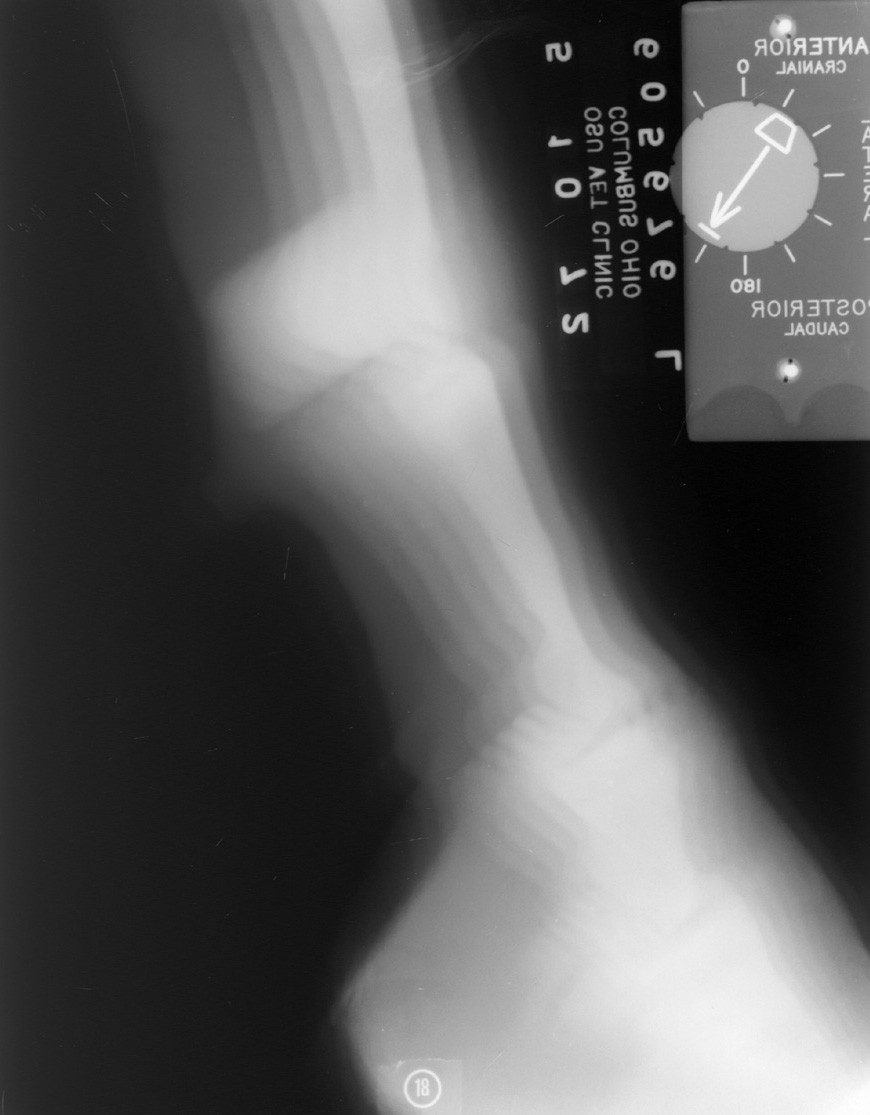

Motion: Patient motion resulting in a blurred image.